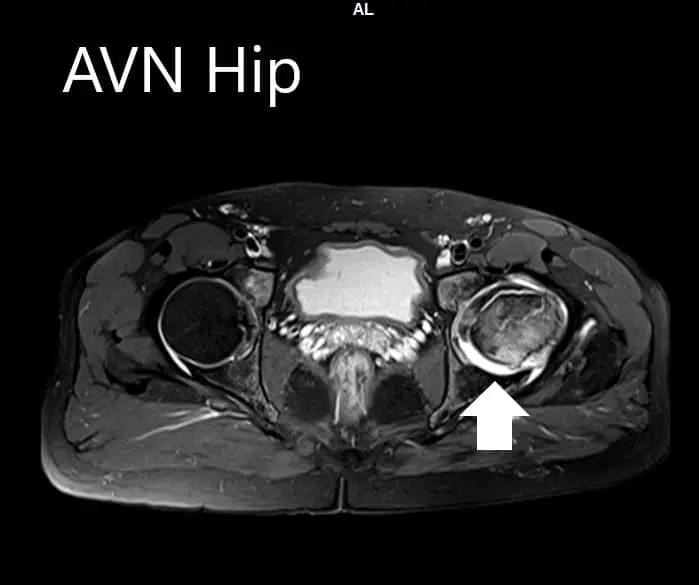

An MRI was obtained for diagnostic confirmation and staging of the disease. The left femoral head was collapsed with irregular contour and showed areas of altered signal intensity with a line of demarcation. Hypointense areas both on T1WI & T2WI seen in head suggestive of sclerosis. Surrounding marrow edema was seen

The left hip had advanced avascular necrosis with a collapse. The right hip was uninvolved presently. He was educated about the worsening collapse of the hip joint leading to his symptoms. Although the patient was young, he was advised a total hip replacement surgery in view of the collapse of the head of the femur with arthritis.